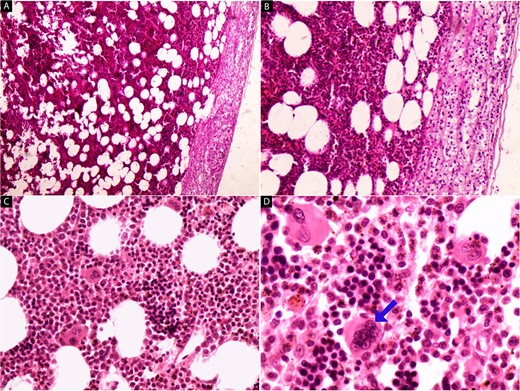

We report the case of a 45-year-old female, who presented to our hospital because of a mass on the right adrenal gland that was discovered incidentally during a periodic echocardiogram without any symptoms on the patient. The patient declared a history of excisional biopsy for a benign breast mass, a medical history of medication-controlled hypertension for 5 years, and Type 2 diabetes for 10 years but the family history was unremarkable. Laboratory investigations, including complete blood count and biochemical markers, were within normal limits. Imaging studies were performed, including contrast-enhanced computed tomography (CT) of the abdomen. The CT scan revealed a large, well-defined, heterogeneous mass measuring 13 × 12 × 9.5 cm, located in the right adrenal gland. The mass contained areas of high attenuation, suggesting recent hemorrhage, along with fat-density areas consistent with adipose tissue (Fig. 1). There were no signs of invasion into adjacent structures or lymphadenopathy. Based on the clinical presentation and radiological findings, the provisional diagnosis was a hemorrhagic giant adrenal myelolipoma. The patient underwent a right open adrenalectomy to address a large mass and minimize potential complications such as hemorrhage. Intraoperatively, a large, encapsulated mass was found in the right adrenal gland. The mass was carefully dissected from surrounding tissues, and the adrenal gland was removed and sent to the pathology department. There were no intraoperative complications. Upon gross examination, a mass with a total weight of 44.5 g was observed, measuring 15 × 10.5 × 5 cm. The mass displayed encapsulation and exhibited a rubbery to cystic consistency, with areas of hemorrhage evident. The cut surface revealed a heterogeneous composition, ranging in color from yellow to black and presenting a gelatinous texture. Multiple sections of the specimen were subsequently submitted for further analysis (Fig. 2). Microscopic examination revealed a mixture of mature adipose tissue and hematopoietic elements, including myeloid and erythroid cells. Focal areas of hemorrhage and hemosiderin deposits were observed within the tumor (Fig. 3), consistent with the radiological findings. Histopathological examination confirmed the diagnosis of a hemorrhagic adrenal myelolipoma. There was no evidence of malignancy. The patient had an uneventful postoperative recovery and was discharged on the 5th day after surgery. Follow-up at 6 months showed no complications, and imaging studies demonstrated no evidence of tumor recurrence. The patient continues to be asymptomatic and is under regular surveillance.

Contrast-enhanced CT scan showing a heterogeneous mass measuring 13 × 12 × 9.5 cm in the right adrenal gland (arrows).